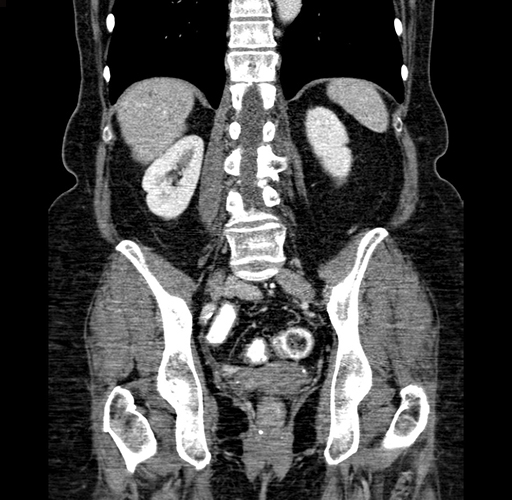

Pre-Chemo: Coronal Venous